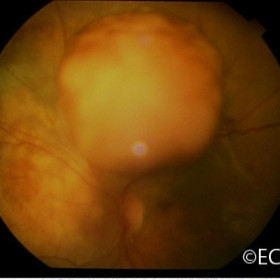

Ciliary body melanoma

Ciliary body melanoma behind the iris as seen through a dilated pupil